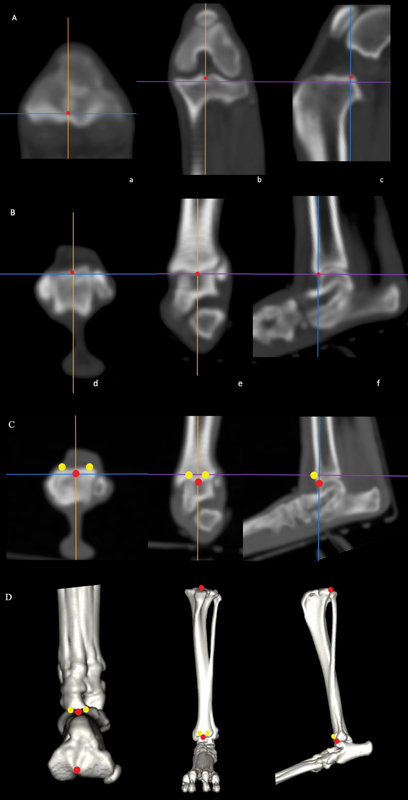

Study design:  We performed a morphological study of the tibia and comparison with MPL grade, and established a new parameter, metatarsal orientation relative to the orientation of the tibial tuberosity, the proximal tibia metatarsal angle (PTMTA). The distal tibia metatarsal angle was also established, and tibial torsion angle (TTA), mechanical medial proximal tibial angle, medial distance of the tibial tuberosity/proximal tibial width, and crural rotation angle were compared among the grades of MPL.

Results:  The PTMTA was significantly higher in grades 3 and 4 than in the normal group. TTA, medial distance of the tibial tuberosity/proximal tibial width, and mechanical medial proximal tibial angle were significantly higher in grade 4 than in the other grades, which is consistent with previous reports. A correlation was also observed between the PTMTA and the TTA.

Conclusion:  The PTMTA functioned as a parameter that included elements of the distal tibia metatarsal angle, TTA, and medial distance of the tibial tuberosity/proximal tibial width, and is considered clinically useful because it can be visually ascertained during palpation. Our results may play a major role in surgical decision-making in the treatment of MPL.